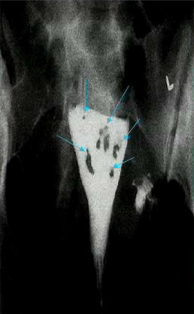

What are these?

Hysteroscopy image of the ostea inside of the uterus that are the openings that enter the fallopian tubes